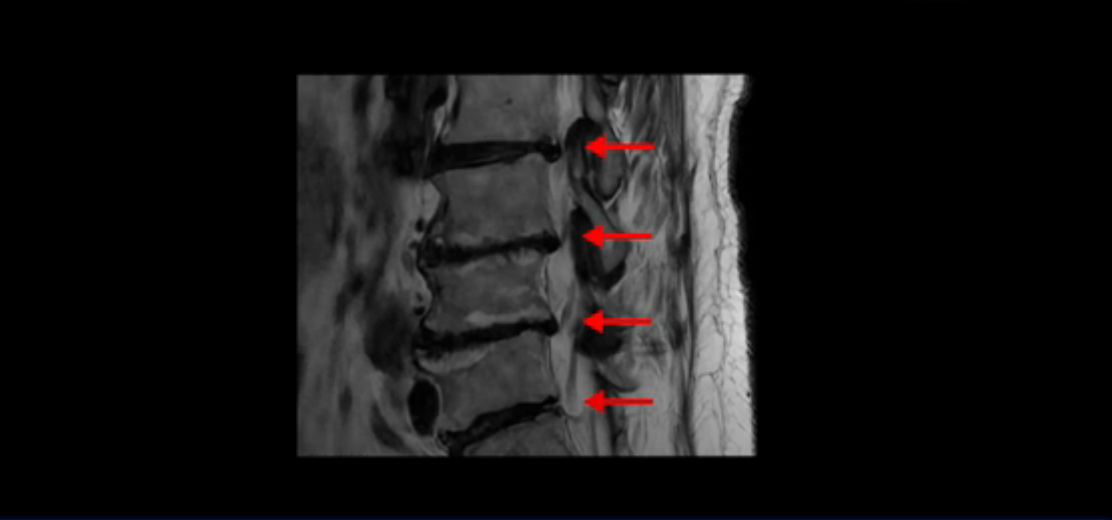

보시다시피 이 환자분은 허리 여러 마디가 다 안 좋습니다. 4마디 디스크 높이가 심하게 주저 앉았습니다.

신경이 빠져나가는 추간공들이 좌우 다 좁아져 있고

척추관도 좁아져 있습니다.

이렇게 신경 구멍들이 좁아져 있어서 신경눌림 증상이 엉덩이와 다리에 생기는데, 이런 증상들은 근육과 매우 밀접한 관련이 있습니다.